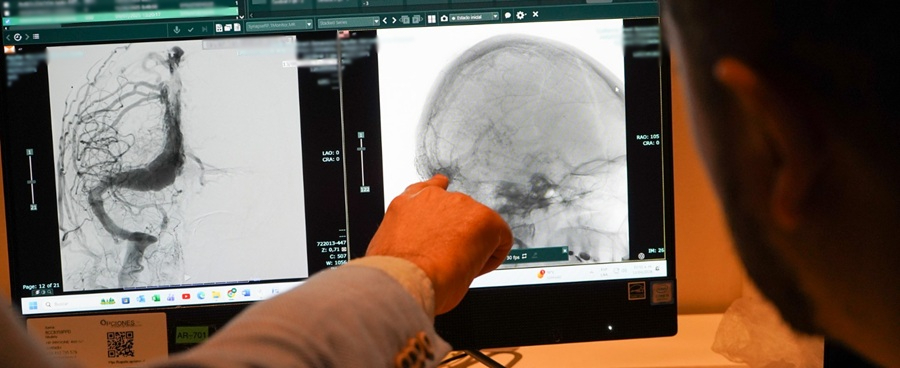

Emergencia con legumbre movilizó a dos equipos del HGGB

para salvar la vida de un menor